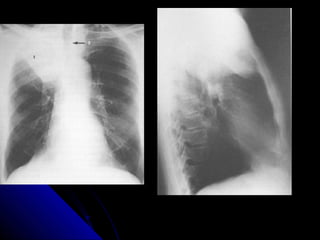

CCoollllaappssee

CCoommmmoonn ccaauussee ooff wwhhiittee lluunngg..

CCoollllaappssee lleeaaddss ttoo lloossss ooff vvoolluummee..

TThhee nnoorrmmaall llaannddmmaarrkkss aarree ddiissttoorrtteedd..

LLooookk aatt tthhee lluunngg ffiieellddss:: RR>>LL..

LLooookk aatt tthhee ddiiaapphhrraaggmm:: RR>>LL..

LLooookk ffoorr tthhee oobblliiqquuee ffiissssuurree..

TThhee hheeaarrtt aanndd tthhee ttrraacchheeaa..

TThhee bboorrddeerrss ooff tthhee hheeaarrtt..